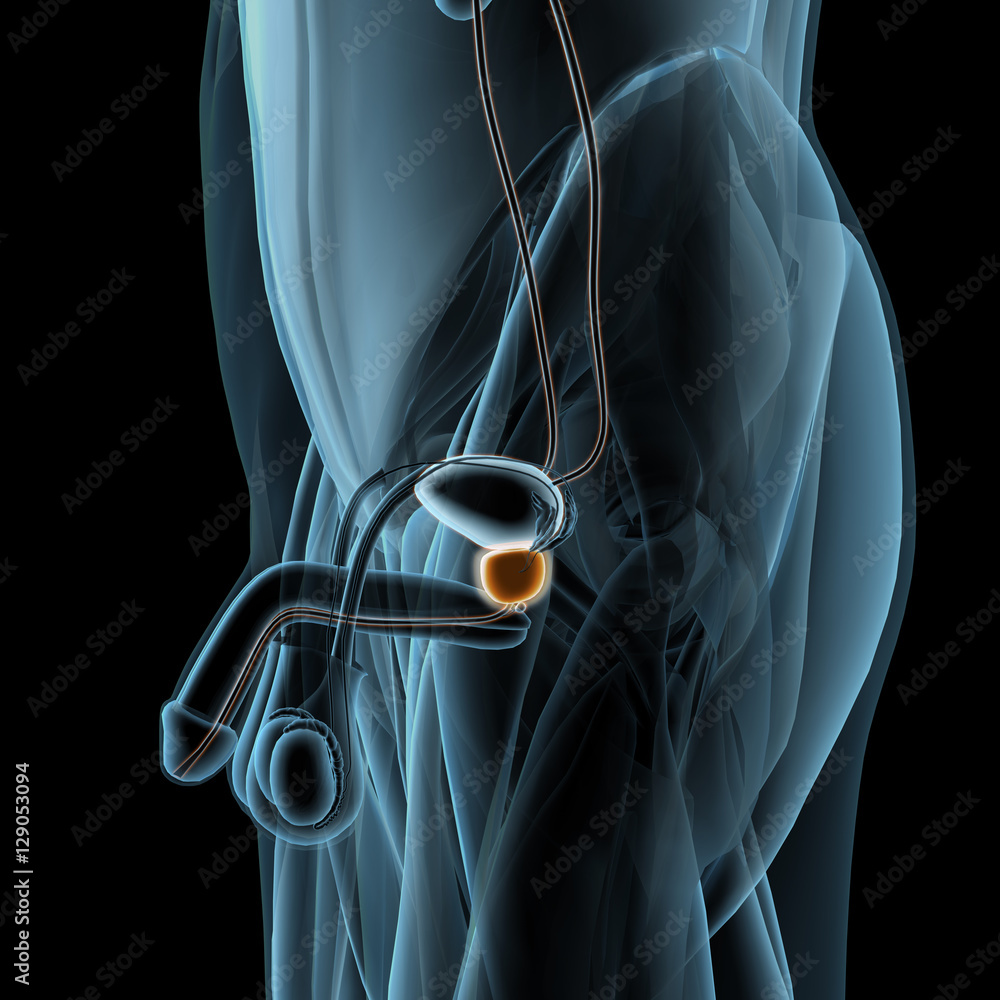

Male Genital Injuries